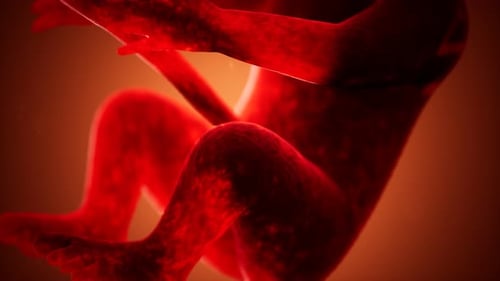

Animation médicale 3D d'un foetus humain

Par doctor-graphicsUn abonnement à excellent rapport qualité-prix dès 16,50 $US/mois